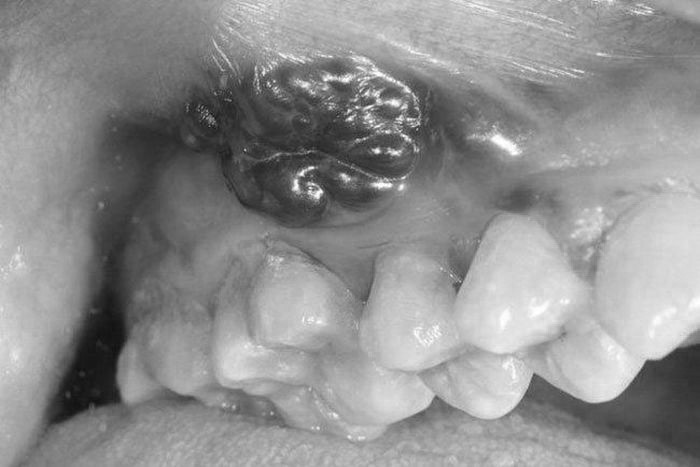

Ngày 11/5, Bác sĩ chuyên khoa II Nguyễn Quốc Dũng - Khoa Phẫu thuật Đầu mặt cổ - Bệnh viện K (Hà Nội) cho biết, đơn vị vừa phẫu thuật thành công trường hợp ung thư lợi hàm dưới.

Bệnh nhân là ông Nguyễn Văn N. (71 tuổi, trú ở Nam Định) vào viện trong tình trạng u to lấp đầy miệng khiến người bệnh không ăn uống được. Sáu tháng trước, ông N. thấy trong miệng xuất hiện khối sùi loét, đau, ăn uống vướng. Nhưng bệnh nhân nghĩ bị nhiệt miệng nên không khám.

Hai tuần trước khi nhập viện, khối u phát triển nhanh khiến ông N. không ăn, không nói được, thỉnh thoảng chảy máu qua đường miệng. Người nhà đã đưa đi khám tại tuyến dưới. Bác sĩ nghi ngờ ông N. bị ung thư nên chuyển tuyến lên Bệnh viện K.

Các xét nghiệm lâm sàng và cận lâm sàng cho thấy ông N. mắc ung thư lợi hàm dưới, có tiền sử hút thuốc lá và uống rượu nhiều năm. Bệnh nhân được chỉ định phẫu thuật để xử lý vét hạch cổ, cắt rộng u, cắt đoạn xương hàm dưới, tạo hình.

Sau mổ, sức khỏe bệnh nhân ổn định. Bác sĩ Dũng cho biết, dự kiến sau 10 -14 ngày bệnh nhân sẽ chuyển điều trị xạ trị bổ trợ, tái khám định kỳ theo hẹn.

Bác sĩ Dũng khuyến cáo, hút thuốc lá và uống rượu là những nguyên nhân chính gây ra bệnh ung thư lợi nói riêng và các loại ung thư đầu cổ nói chung.

Ngoài ra, thói quen xấu như vệ sinh răng miệng kém, răng lệch lạc,... có thể gây nên những tổn thương cơ học trong khoang miệng tạo điều kiện thuận lợi cho ung thư phát triển.